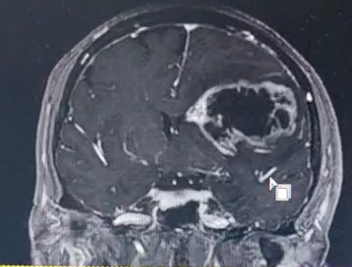

在河北省人民医院,一位63岁女性患者正面临 “生死时速” 的考验。患者因 “右上肢肌力下降伴部分失语5天,加重1天” 入院,病情进展较快——入院仅1天便完全失语,偏瘫症状进一步加重。两院专家联合评估,制定个性化手术方案。

术中利用导航、超吸、电生理等辅助手段,王虎主任成功将肿瘤全部切除,术后患者症状得到明显改善。